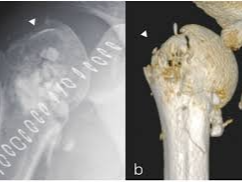

어깨뼈 골절은 어깨 주변을 구성하는 여러 뼈 중 하나가 부러지는 상태를 의미합니다. 어깨는 단순한 관절이 아니라 여러 뼈와 인대, 근육이 복합적으로 연결된 구조이기 때문에 골절의 종류도 다양하게 나타납니다. 흔히 발생하는 골절 위치는 견갑골, 쇄골, 상완골 근위부입니다. 특히 낙상 사고나 교통사고에서는 상완골 근위부 골절이 자주 발생합니다.

이 중에서도 상완골 근위부 골절은 고령자 낙상 사고에서 매우 흔하게 나타나는 골절이며, 경우에 따라 금속 핀이나 금속 플레이트를 이용한 고정 수술이 필요할 수 있습니다.

- 초기 진단

- X-ray 촬영

- CT 검사

- 골절 위치 확인